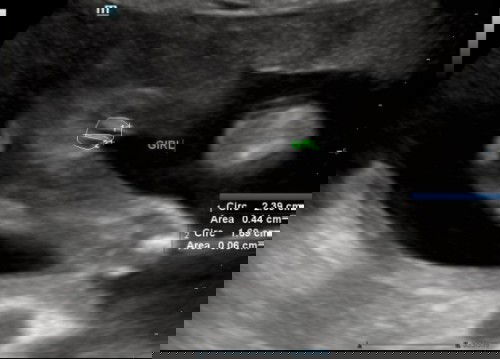

Hi mommies semua, nak pinjam mata ibu2 jap hehe rasa ni mmg baby girl kerπ€£ sy tanya doktor da . Doktor kata mmg girl sbbnya xnampak langsung penampakan pistol . Mula2 17week scan di KK doktor pun kata mcm girl sbb xde nampak pistol sbb nampak garis tp samar2 . Ni sy buat detail scan di swasta 21week . Doktor check tgk mmg dia tunjuk burger terus sbb ad garisanπ tp tulakn pinjam mata ibuibu jeπ₯°π₯°first baby untuk sy juga . Terima kasih ibu ibu semuaπ₯° #ingintahu #firstbaby